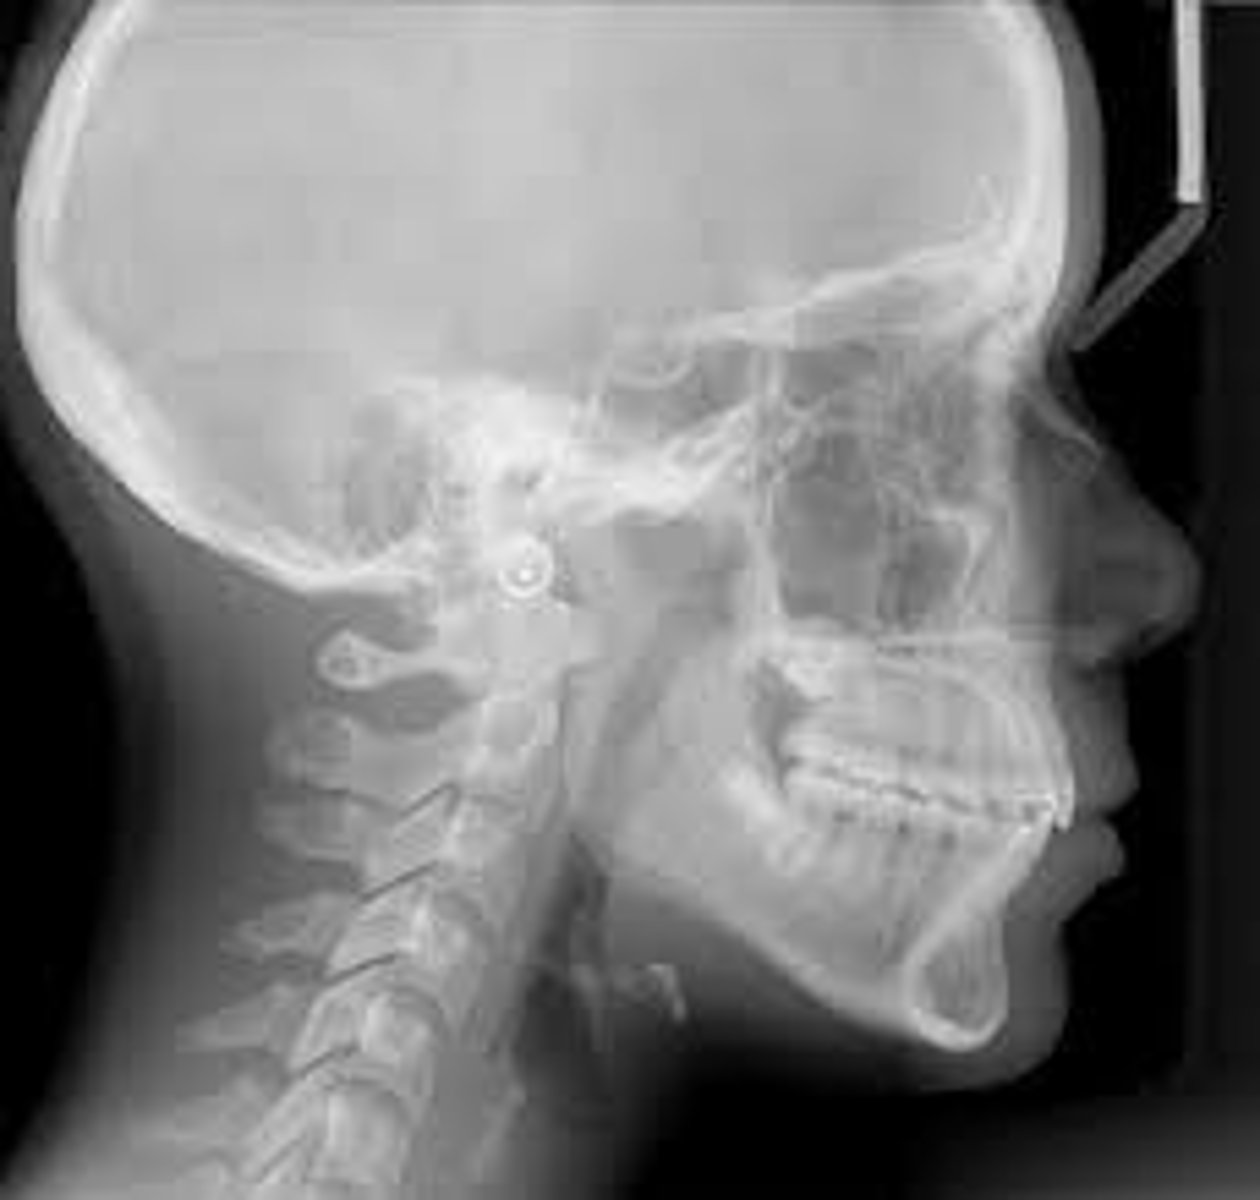

Cephalometric

mainly used in ortho but it helps to see development